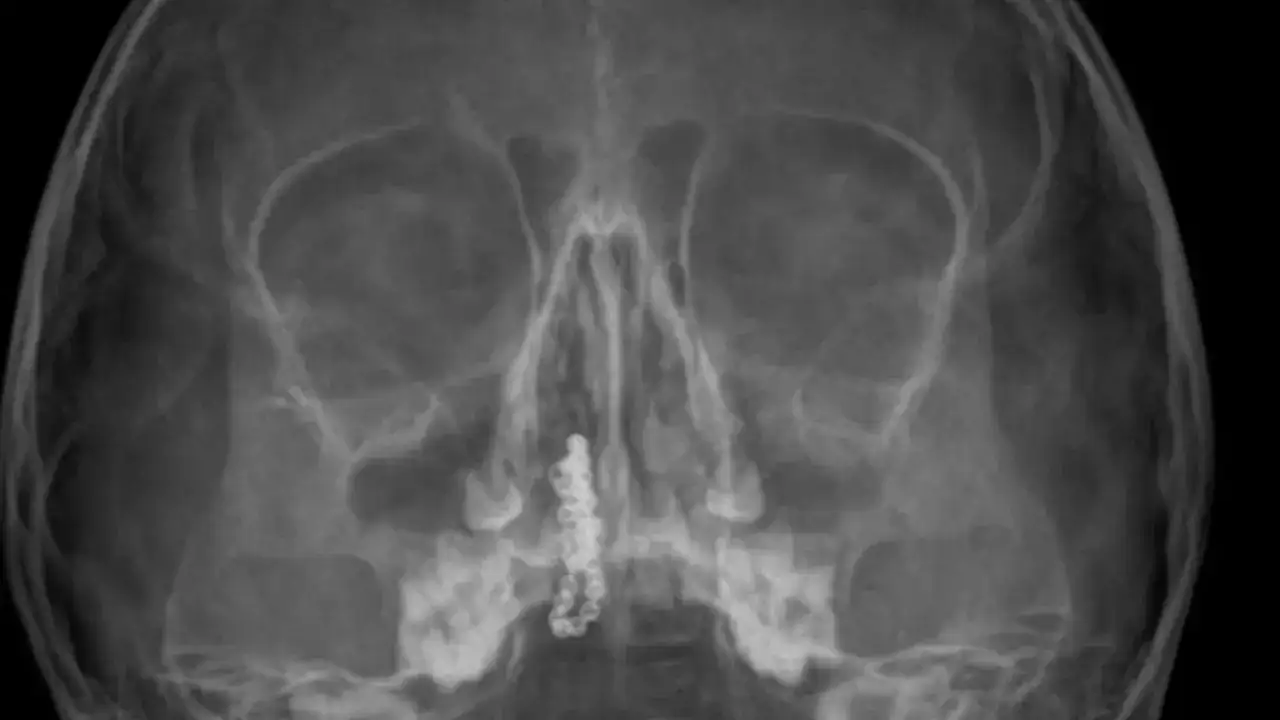

Kentte yaşayan Gökhan-Nalan Tekin çifti, yaklaşık 4 ay önce şiddetli burun kanamasının yanı sıra akıntı şikayetleriyle kızları Polen'i, bir özel hastaneye götürdü. Burada röntgeni çekilip, tetkikleri tamamlanan küçük kıza, iddiaya göre enfeksiyon teşhisi konulup, ilaç verildi. Eve dönen aile, kanama ve akıntının geçmemesi üzerine bu kez Rize Devlet Hastanesi'ne giderek Kulak Burun Boğaz Polikliniği'ne başvurdu. Devlet hastanesindeki doktorun incelemesi ve kapsamlı röntgen çekilmesi sonrası Polen'in burnunda metal cisim olduğu fark edildi. 2 yıldır burunda kaldığı değerlendirilip, küçük top şeklinde tırnak makası zinciri olduğu belirlenen cisim, başarılı ameliyatla çıkarıldı. Bir süre tedavisi sürdürülen Polen, sağlığına kavuşunca taburcu edildi. Özel hastane yetkilileri, konuyla ilgili açıklama yapmazken; aile suç duyurusunda bulunacaklarını söyledi.

Kızının burnundan sürekli siyah renkte akıntı olduğunu anlatan Gökhan Tekin, "Çocuğumun burnundan kanama ile sürekli siyah akıntı geliyordu. Özel hastaneye götürdüm. Özel hastanede film çekildi, hiçbir bulguya rastlanılmadığı söylendi. O siyah leke de enfeksiyona dayalı olan bir şey olduğu bize söylendi. Eve geldik, akıntı sürmesi üzerine bu kez devlet hastanesine başvurduk. Burunda metal zinciri fark ettiler. Böyle bir ihmalkarlık olabilir mi? Özel hastaneye gidiyoruz, paramızla rezil oluyoruz. Zincir, 2 yıldır burnunda ve devletimizin hastanesinde iyi bir doktorumuz zinciri ortaya çıkarıyor, kızım ölümden dönüyor. Ben sonuna kadar bu işin peşini bırakmayacağım. Sonuna kadar hukuk mücadelesi vereceğim. Bu da diğer hastalarımıza ibret olsun. İşte, bakın koca bir zincir. 'Bulguya rastlanılmadı' deniliyor" dedi.

Kızının ameliyat sonrası durumunun iyi olduğunu söyleyen Tekin, "İnanır mısınız bize 'Evde soba mı yanıyor? Acaba kömür isten dolayı mıdır bu?' dendi. Böyle bir şey olabilir mi? Ameliyattan çıkan parmağım kadar zincir. Devlet hastanesindeki doktor da 'Bu nasıl gözden kaçılabilir? Böyle bir pozisyon nasıl görülmeyebilir?' yorumunda bulundu. Allah'a şükür olsun atlattık. Şu anda durumu, vaziyeti iyidir. Ben şuna inanıyorum doktor da bir şans işidir. Bakın paramızla özele gideriz ya hani bizde, daha iyi ilgilenirler. Oysa devlet hastanesindeki doktorumuz olayı meydana çıkardı" diye konuştu.